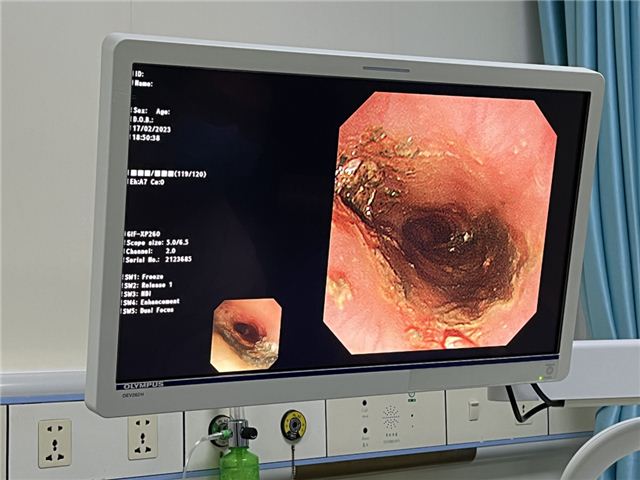

小小电池,大大麻烦 小孩子对世界充满了好奇,什么东西都喜欢放在嘴里尝尝,尽管家长一再谨慎看护,还是难免百密一疏。 …… 近日,长治市妇幼保健院儿内二科(儿童消化专科)接诊了一名10个月大的宝宝,宝宝的父母焦急万分,原来是宝宝误吞了纽扣电池!幸运的是,宝宝胸部X线片提示:纽扣电池位于食管上段狭窄处,暂未进入胃内。 要知道,一旦电池不能及时排出体外,体内液体将腐蚀电池外壳,致使电池中的电解液漏出,在体内发生化学反应,致使内脏灼烧、腐蚀而糜烂甚至穿孔等,不仅需要外科手术介入,更会对孩子造成不可逆的永久伤害! ❀ 误吞纽扣电池 “10个月大小的女宝宝因误吞纽扣电池已有2小时,需进行急诊内镜下取出。”当天,儿内二科主治医师郝旭东接到急诊电话通知。接到通知后,郝医生立刻警惕起来,因纽扣电池不同于普通的异物,极易造成食管、胃、肠等消化道损伤,严重者会危及生命,随即立刻请示儿内二科赵枫主任。考虑到患儿年龄小,并且风险较高,于是立刻通知麻醉科,做好手术相关准备。 时间就是生命,每提前争取1分钟,就可减少纽扣电池对患儿的损伤。郝医生在谈话间迅速与患儿家属沟通,告知其风险性、利害关系后,快速跑入内镜室,紧张的救治即刻开始。患儿胸部X线片提示纽扣电池位于食管上段狭窄处,10个月大的患儿不同于成年人,操作空间有限,加大了操作难度,儿内二科、麻醉科医生护士争分夺秒,在患儿全身麻醉下,采用无痛电子胃镜联合异物钳,顺利取出一枚直径1.5厘米的圆形纽扣电池。 警报虽然解除,但术中发现患儿食管粘膜后壁侧发黑、质脆,取出后可见患儿食管上段距门齿约12-16cm处后壁大范围电灼伤。郝医生考虑到,可能由于患儿呕吐导致电池短路引起食管损伤,可能出现感染、食管穿孔、水肿压迫气管影响呼吸、出血、食管气管漏等近期并发症,可能出现食管狭窄、吞咽困难等远期并发症。给予留置胃管,少量多次喂养,嘱咐患儿头高脚低体位,避免返流对症治疗。 2023年3月2日,为了解患儿恢复情况,儿内二科再次联合麻醉科采用无痛电子胃镜观察患儿食管壁情况,患儿食管壁恢复良好,办理出院。患者家属万分感激,专程来到儿内二科赠予一面锦旗。 ❀医生提醒: 误吞异物是医院急诊较常见的儿童意外伤害事件。家长要警惕“祸从口入”,孩子进食时切勿逗笑及呵斥孩子,加强高危物品的保管,尽量选择一体合成的玩具等。要高度重视误服电池的危害性,一旦发生儿童误服电池,应立即就医,尽快取出,不管电池有多小,都不要存在侥幸心理,避免给孩子造成更大的损伤。万幸的是,电池相对偏大,没有通过幽门进入小肠,且家长发现及时,电池仍然停留在胃里。否则,孩子将面临开腹手术! 带您走进儿内二科 儿童保健部儿内二科是以消化内科专业为特色的市级重点专科,是集临床、教学、科研于一体的临床业务科室,设有儿童重症监护病房,科室开放床位44张,专业技术人员26人,其中高级专业技术职称3人,硕士学位4人,专业队伍实力雄厚,拥有先进的儿童电子胃镜、儿童电子肠镜、儿童消化道CT等设备,儿童无痛胃肠镜检查和无痛胃镜取异物等技术居本地区领先水平。我院开展的检查项目有:幽门螺杆菌检测、乳糖不耐受检测、胃食道PH检测、消化道病原检测等。目前诊疗的疾病有:儿童反复呕吐、胃食管反流病、急慢性胃炎、消化性溃疡、急慢性腹痛、腹泻等常见病多发病;对先天性幽门肥厚/狭窄、消化道出血、消化道息肉、胰腺炎、婴儿肝炎综合征、肝功能衰竭、炎症性肠病、坏死性小肠炎、腹膜炎等疑难病症的诊疗方面积累了丰富的经验。本着“仁心善术、惠泽妇儿”的精神,竭诚为广大儿童服务。 专家简介 赵枫 长治市妇幼保健院小儿消化内科主任,主任医师,长治医学院兼职副教授,为“山西省百千万卫生人才骨干精英人才”、“长治市学科技术带头人”。兼任华北地区儿科学组常务委员、长治市新生儿学组副主任委员、山西省医学会儿科分会重症学组副组长、 国家级住院医师规范化培训师资等,发表国家级、省级论文数十篇。曾在美国旧金山太平洋医疗中心研修,先后在北大一院,北京儿童医院,山西省儿童医院进修学习。擅长儿童消化系统、呼吸系统、神经系统及危重症疾病的诊治。 出诊时间:每周三、日上午;周五下午 郝旭东 主管医师,中共党员,长治市妇幼保健院儿科医师,兼任中国妇幼保健协会小儿消化微创学组全国青年委员、中国医师协会儿科医师分会儿童消化内镜学组委员。擅长小儿消化道疾病的诊治,以及儿童胃镜、肠镜的操作,在长治地区率先开展儿童胃肠镜检查及诊疗技术。 出诊时间:每周一至周五下午 咨询电话: 0355-2052654 部分图片来源于网络,如有侵权,请联系删除 供稿 | 儿内二科 贺东伟 审核 | 儿内二科 赵枫 编辑 | 宣传科 王慧丽 排版 | 实习生 潘文华 请长按二维码关注,获取更多妇幼资讯